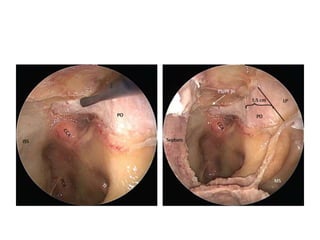

Right sided anterior petrosectomy on a cadaver dissection: intradural exposure

and operative field. PCA Petrous carotid artery; DPA drilled petrous apex; IPS

inferior petrosal sinus; BA basilar artery; VI 6th cranial nerve; AICA anterior inferior

cerebellar artery; P pons; V 5th cranial nerve

NOTE Inferior petrosal sinus at CLIVUS